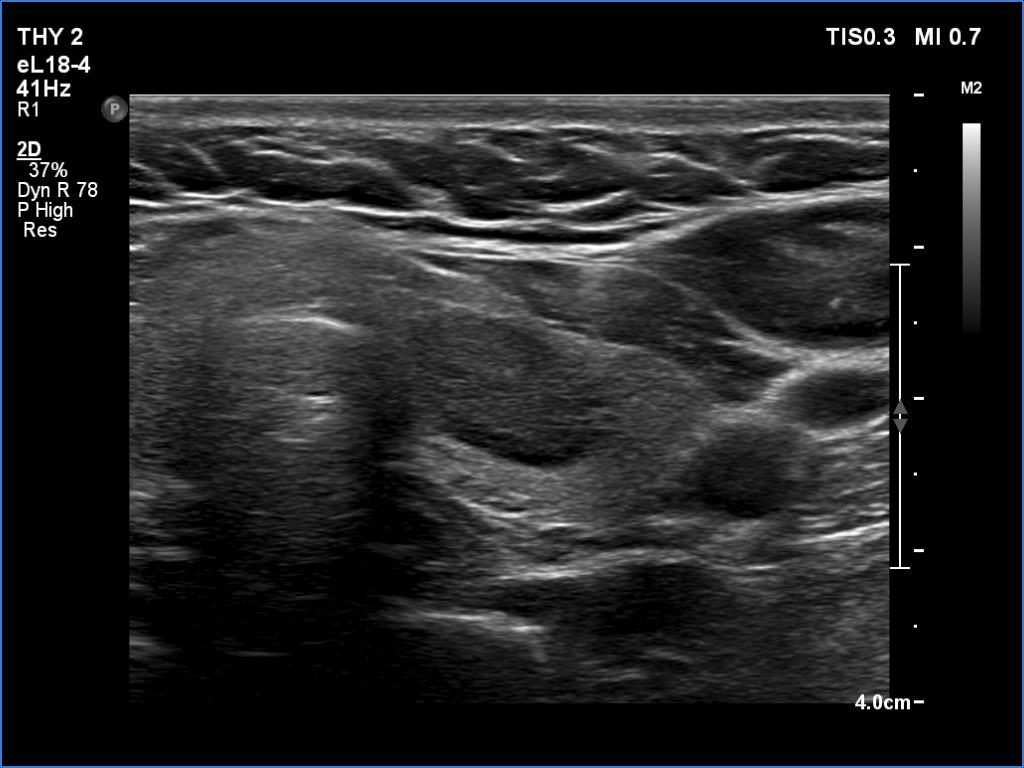

Ultrasonography. The thyroid was echonormal. There was a moderately hypoechoic lesion in the lower pole of the right lobe. The lesion presented no suspicious findings.